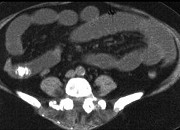

- 单项选择题男,30岁, 有胆结石病史,近日腹痛、腹胀, CT检查如图,应诊断为  (    )

- A、胆石症

- B、胆石性肠梗阻

- C、肠结核

- D、小肠克罗恩病

- E、小肠淋巴瘤